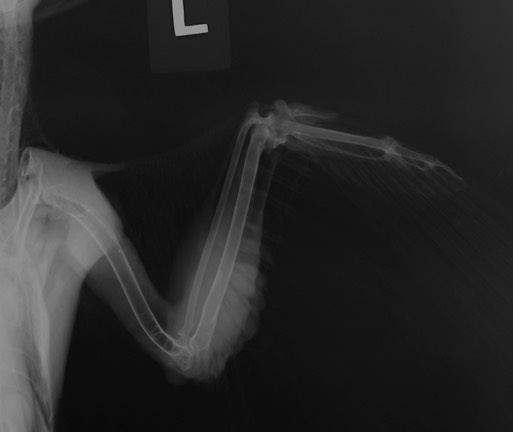

Cooper’s Hawk 18-582

18-582 was found in a yard in a residential area of Othello, WA. He also had a suspicious looking wound on the left elbow. A radiograph showed hairline fractures in the ulna and a badly damaged elbow.

Further examination revealed both entrance and exit wounds.